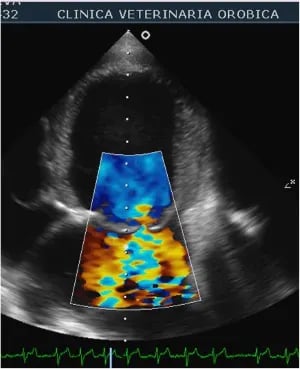

Moderne apparatuur en technieken #

Voor alle onderzoeken maken we gebruik van moderne echo-apparatuur.